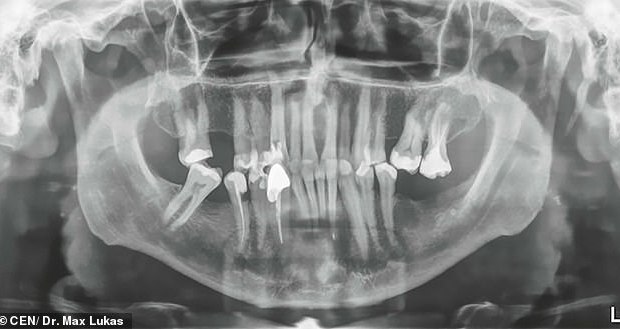

Dr. Saurabh Srivastava ayaa sameeyay qiimeyn isaga oo go’aansaday in uu ka saaro mid kamid ah ilkahiisa oo dhirirkeedu noqday 1.53 inches.

Goor si horreysay, Jarmalka, dhaqtar u gaaroobay ilkaha ayaa bukaan ka saaray iligta ugu dheer caalamka oo dhirirkeedu noqday 1.46 Inches.

Dr Max Lukas oo ka shaqeeya meel ku dhaw Frankfurt ayaa ku guuleystay howlgalka looga saaray dhibbanaha iligta ugu dheer caalamka.